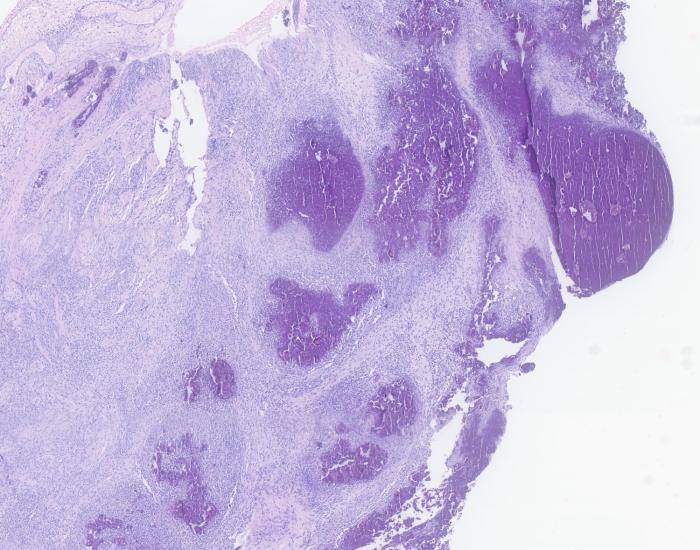

Durante la biopsia se observó salida de material amorfo, semisólido y blanquecino. El estudio histopatológico confirmó que se trataba de una calcinosis circunscrita por la presencia de dépositos de calcio (Figura 6 y 7).

Histológicamente, la CC se caracteriza por la presencia de material basofílico amorfo o granular, rodeado de reacción inflamatoria granulomatosa con macrófagos espumosos y células gigantes multinucleadas, a menudo encapsulado por tejido conectivo fibroso7,12-14.